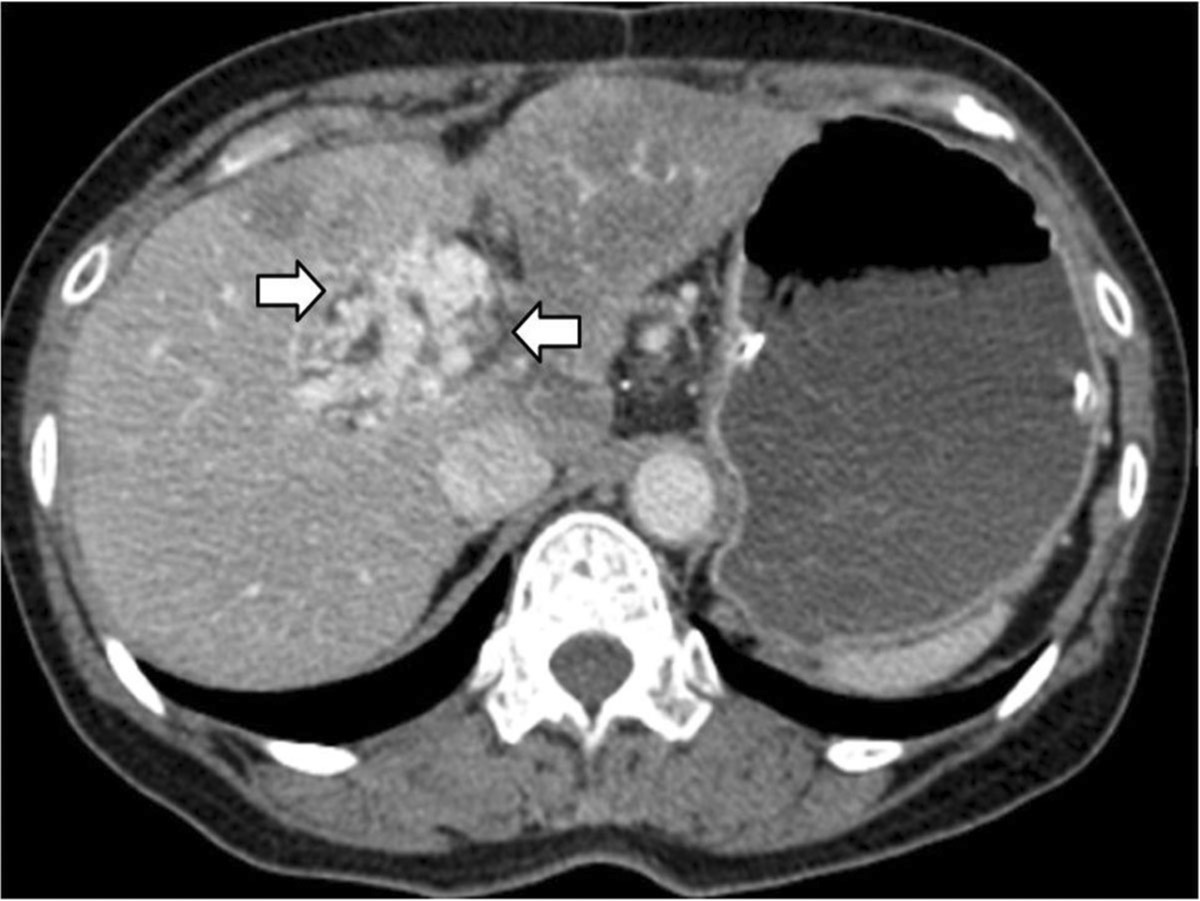

조영증강 복부 전산화단층촬영에서 간-공장 문합부위에 공장정맥류가 확인되었고 주문맥은 폐색으로 인해 관찰되지 않았다 (Fig 1).

Fig. 1.

Fig. 1. Contrast enhanced CT scan of abdomen demonstrate jejunalvarix in hepaticojejunostomy site (arrows) and nonvisualization of the main portal vein.